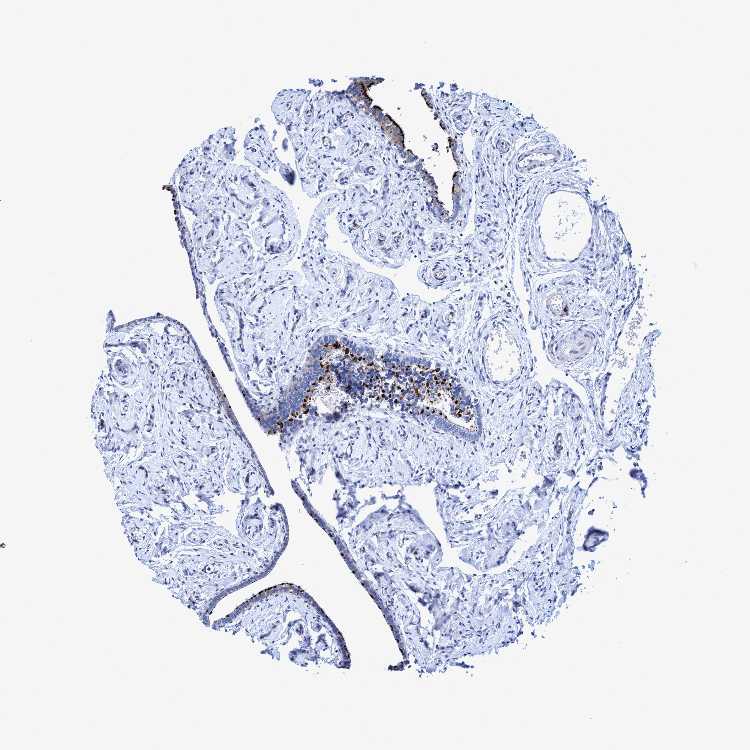

CROCC